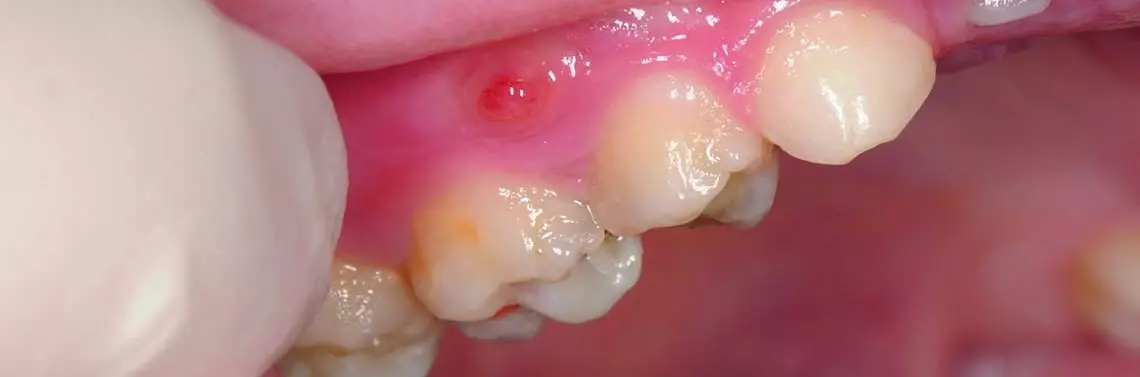

Diagnostyka endodontycznego leczenia dzieci w gabinecie stomatologicznym. Diagnostyka stanów zapalnych miazgi zębów mlecznych – powikłania próchnicowe

Stanów zapalnych miazgi zębów mlecznych można spodziewać się u dzieci w wieku od pół roku do 13 lat. Rodzice rozpoznają zazwyczaj dwa sygnały świadczące o złym stanie uzębienia. Jednym z nich jest ból zgłaszany przez dziecko, drugim wyraźnie widoczne w ustach zmiany próchnicowe, opisywane wówczas jako „czarne dziury”. Lekarz często staje przed dylematem prawidłowej oceny stopnia bólu odczuwanego przez dziecko. Rozstrzygająca będzie zatem duża liczba pytań dodatkowych w trakcie wywiadu z dzieckiem i rodzicami.

• stanem zapalnym tkanek okołowierzchołkowych zęba z martwą miazgą – w zębach mlecznych możliwa jest martwica częściowa nawet przy bardzo zaawansowanym stanie zapalnym okołowierzchołkowym,